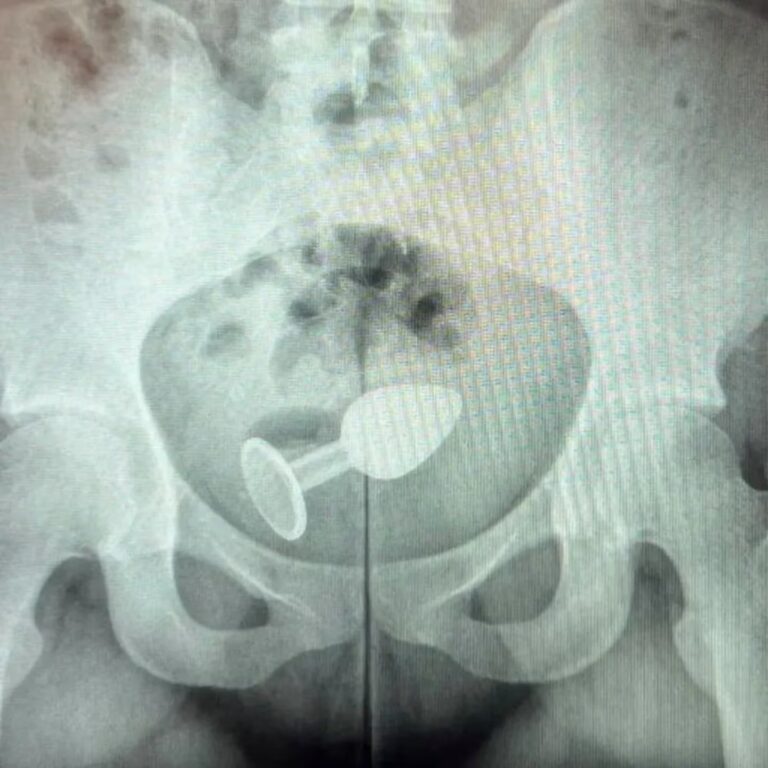

En un hospital de Brasil, los médicos quedaron perplejos al atender a una mujer que sufrió un accidente con un [...]